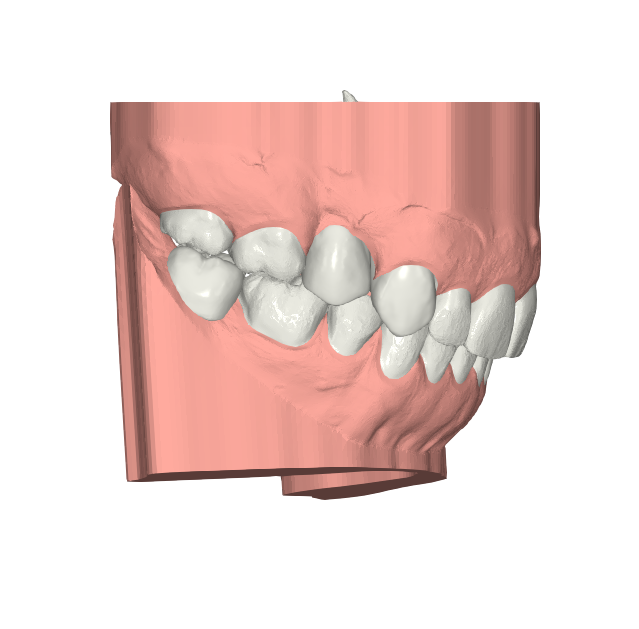

Elevantia Solutions accepted the challenge by designing a treatment plan with Ortho Root Plan Design, a tool that allows orthodontic planning based on the exact position and movement of roots during treatment. This is essential for complex cases because it reduces risks, prevents root damage, and ensures maximum predictability

Ortho Movements

The proposed design corrected midline discrepancies, improved occlusion, and established the foundation for future restorative work. Thanks to this advanced approach, the treatment was safer, more conservative, and highly predictable, providing security for the doctor and confidence for the patient